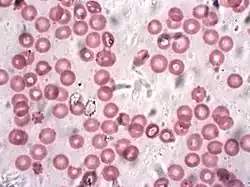

Blood is composed of blood cells suspended in blood plasma. Plasma, which constitutes 55% of blood fluid, is mostly water (92% by volume),[2] and contains proteins, glucose, mineral ions, and hormones. The blood cells are mainly red blood cells (erythrocytes), white blood cells (leukocytes), and (in mammals) platelets (thrombocytes).[3] The most abundant cells are red blood cells.[4] These contain hemoglobin, which facilitates oxygen transport by reversibly binding to it, increasing its solubility.[5] Jawed vertebrates have an adaptive immune system, based largely on white blood cells. White blood cells help to resist infections and parasites. Platelets are important in the clotting of blood.

- 4.7 to 6.1 million (male), 4.2 to 5.4 million (female) erythrocytes:[13] Red blood cells contain the blood's hemoglobin and distribute oxygen. Mature red blood cells lack a nucleus and organelles in mammals. The red blood cells (together with endothelial vessel cells and other cells) are also marked by glycoproteins that define the different blood types. The proportion of blood occupied by red blood cells is referred to as the hematocrit, and is normally about 45%. The combined surface area of all red blood cells of the human body would be roughly 2,000 times as great as the body's exterior surface.[14]